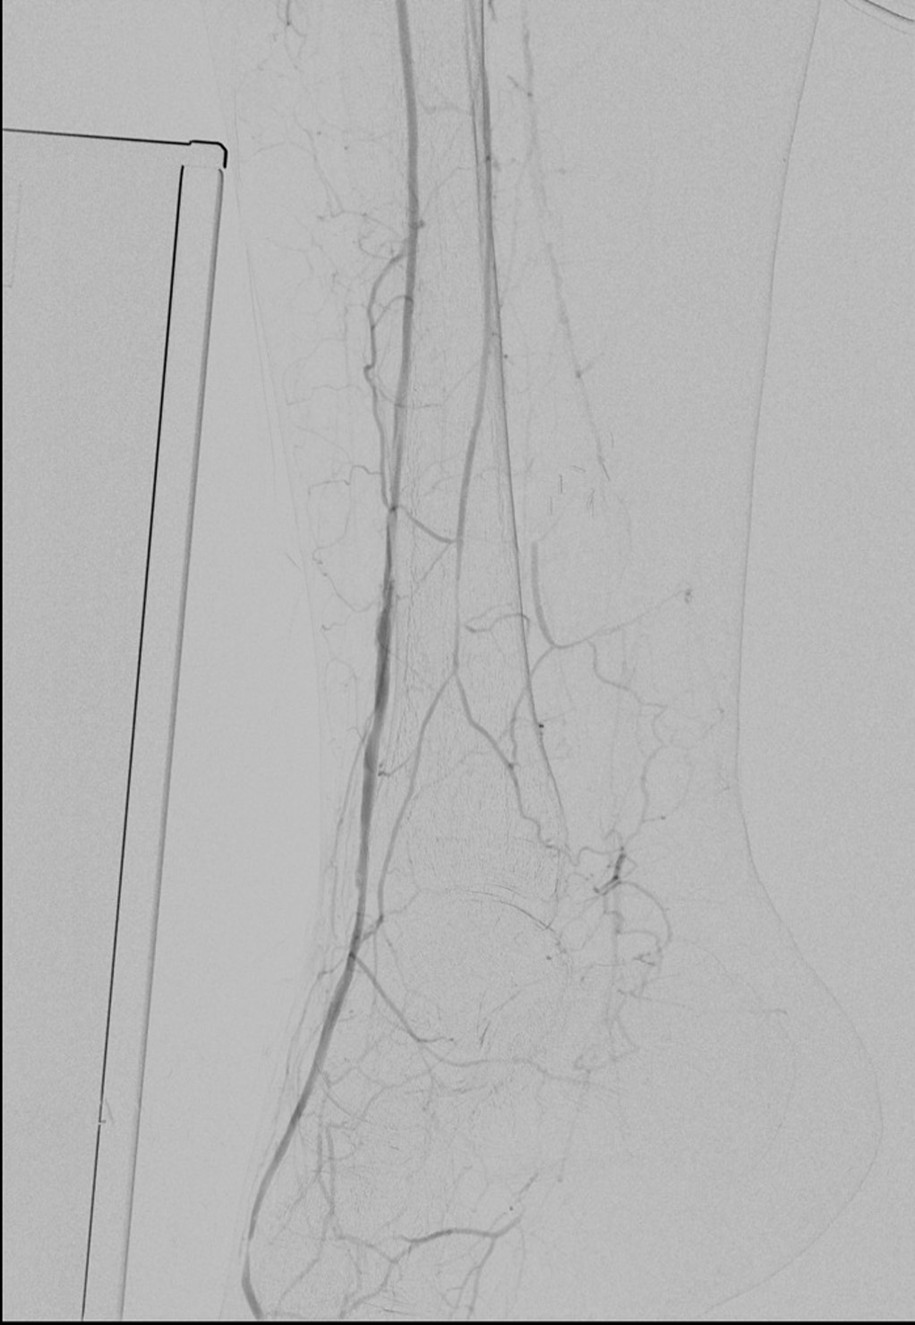

Let me show you one of the first cases I did after returning to Cleveland. I am now practicing at Fairview and Avon Hospitals, premier flagship hospitals in the Cleveland Clinic fleet, on Cleveland’s west side, and a patient arrived while I was on call with sudden onset of pain in his leg from a lack of blood flow. He had occlusive atherosclerotic plaque extending from his external iliac artery to the above knee popliteal artery causing ischemic rest pain.

I contacted LeMaitre Vascular and got in touch with your representative, L. Fisher, who promptly sent the Moll Ring Cutters I needed to perform a remote endarterectomy of the patient’s occlusive external iliac and superficial femoral artery plaque. The technical details of remote endarterectomy are have been covered in my blog (https://vascsurg.me/?s=endore), but in the end, through a 7cm incision in the groin (don’t believe the hype, this is minimally invasive), I restored his arteries to their original open condition. Shown below are the results. It was with great sadness that I heard that the LeMaitre Vascular equipment being sent were the last of the stock available in North America. The patient did very well, with the operation completed well before lunch, and is recovering rapidly from his small wound and big rescue. He gets to walk out of the hospital on two legs, but also with the surety that he avoided a major bypass operation, and avoided the short term gains of stenting from the aorta to the profunda -more peel packs and landfill items and a dubious long term durability. Hey, I even used a XenoSure patch on the common femoral.